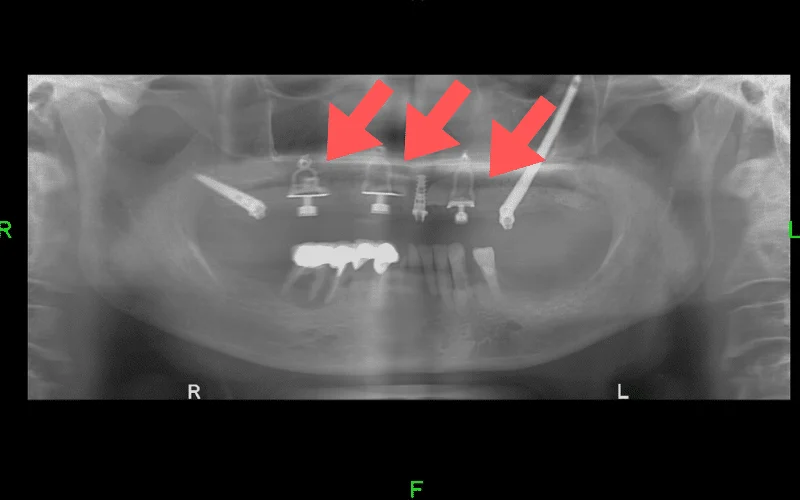

על מנת להבטיח את יציבותה של מערכת השיניים החדשה, שתלים בזאליים לעולם אינם יכולים לעמוד לבד אלא עליהם להיות משולבים עם שתלים דנטליים רגילים.

השתלים הרגילים יעוגנו באזורים שבהם עובי עצם הלסת מאפשר זאת (בדרך כלל בחלקים הקדמיים של הלסת), ואילו השתלים הבזאליים יחוברו באזורים שבהם עצם הלסת דלילה או שכבר אינה קיימת.